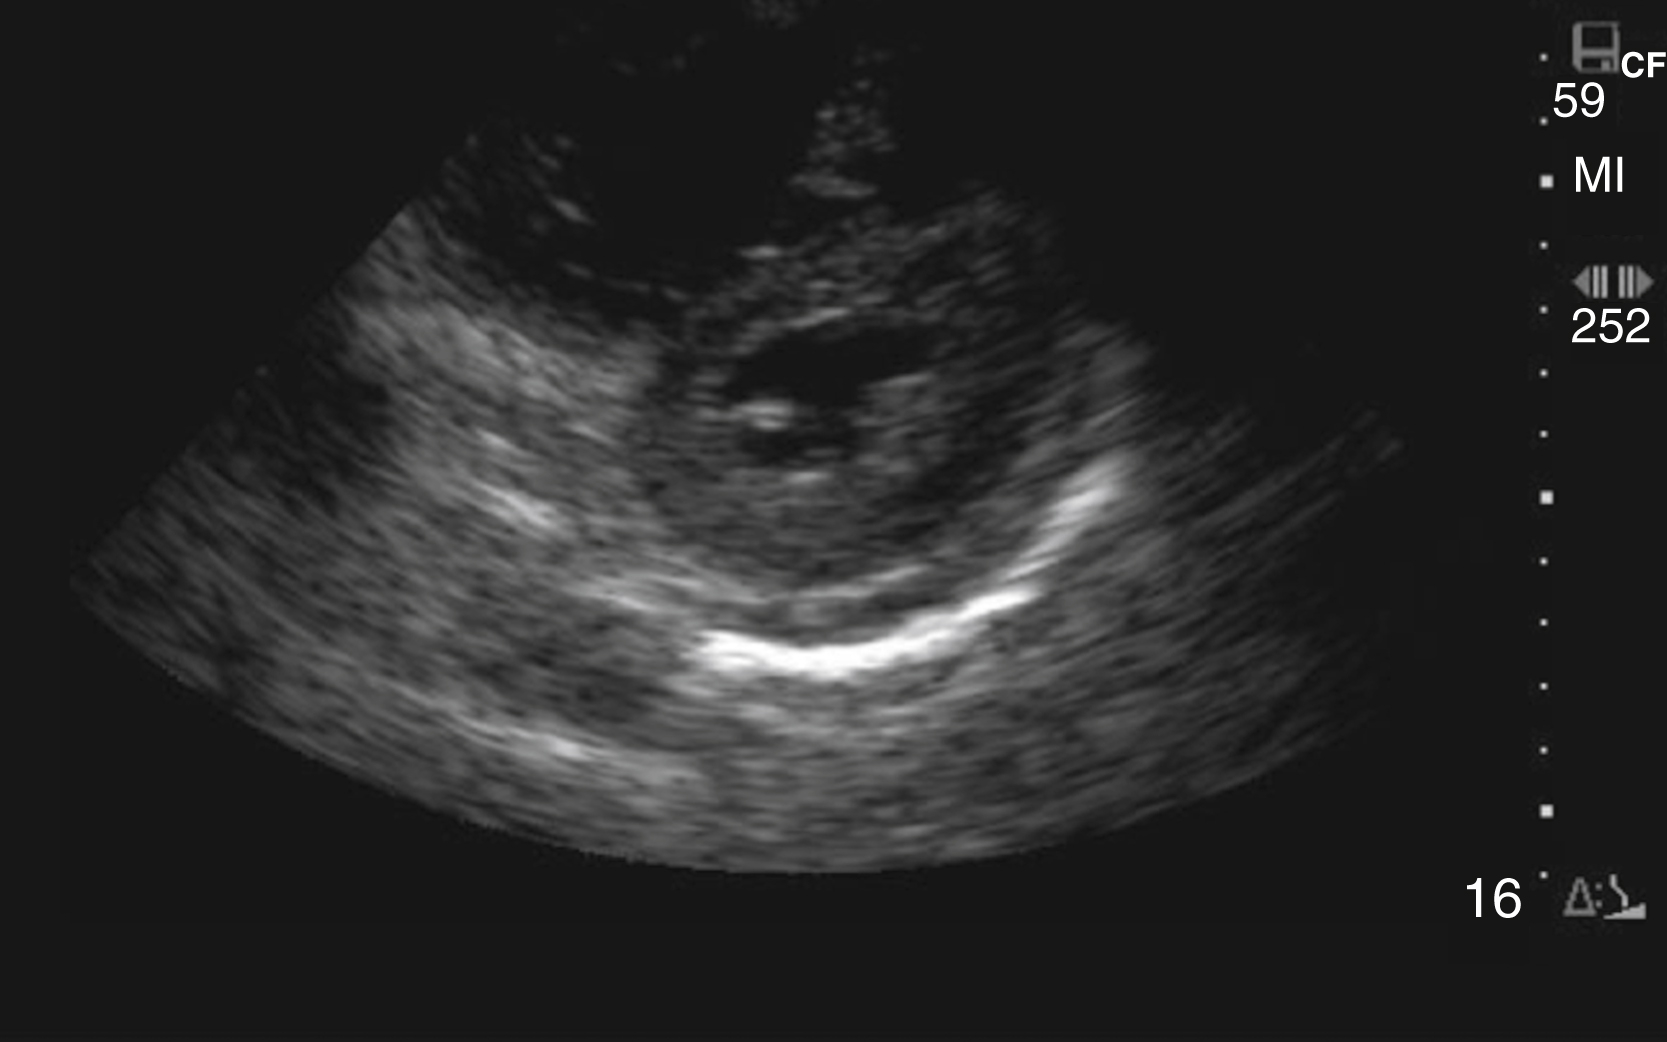

An aortic diameter greater than 3 cm constitutes an abdominal aortic aneurysm, but risk of rupture increases with size and is rare with aneurysms smaller than 4.5 cm ( Fig. e3.8 and Video e3.7 ). A linear echogenic flap, anywhere across the lumen of the aorta, is suggestive of aortic dissection and may be associated with a different Doppler flow pattern on either side of the flap ( Fig. e3.9 and Video e3.8 ). The cardiac US examination may demonstrate an unexplained pericardial effusion, a dilated aortic root (>4 cm), aortic insufficiency, and/or a linear echogenic flap in the descending aorta.

Aortic dissection flap visualized on longitudinal view of the aorta.